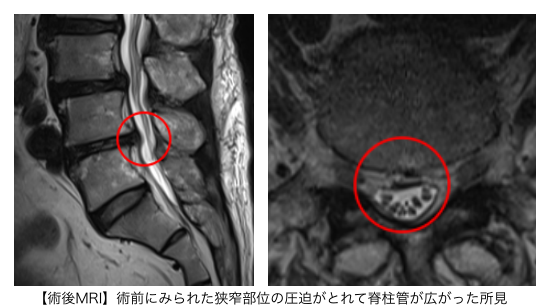

赤い枠で示されている部分(L4/5 )に強い狭窄を認めました。

手術の翌日には足の痛み・痺れが軽減し、その後、徐々に痺れの範囲が狭くなっていきました。術後2ヶ月程度で腰痛はなくなり、痺れも術前を10とすると2まで改善しました。